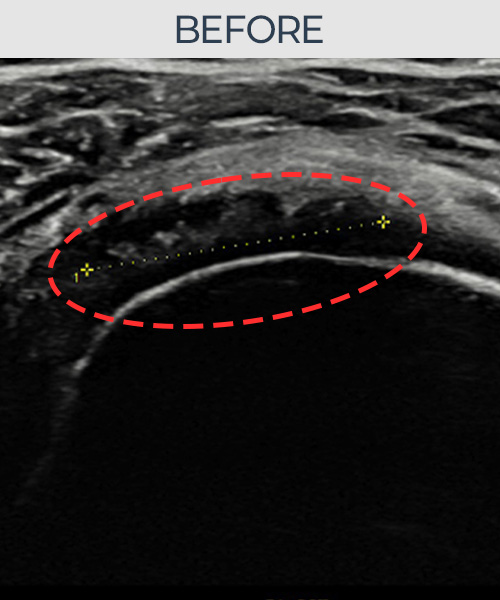

비수술 치료 전후사진

비수술로도 파열된 인대를

물리적으로 재건해 드립니다

인대강화주사만으로는 해결되지 않던 인대파열.

플래티넘정형외과에서는 수술없이도 물리적으로

파열된 인대를 재건

하는것이 가능합니다.